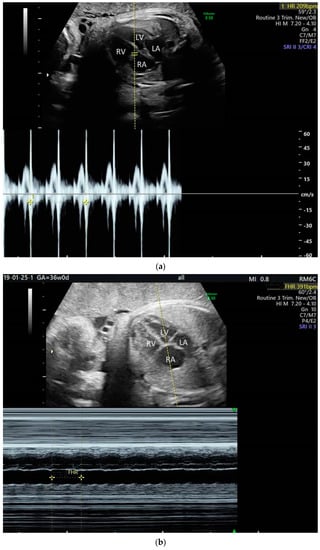

2. The Use of Ultrasound to Assess Fetal Heart Rhythm

5.4. Heart Block